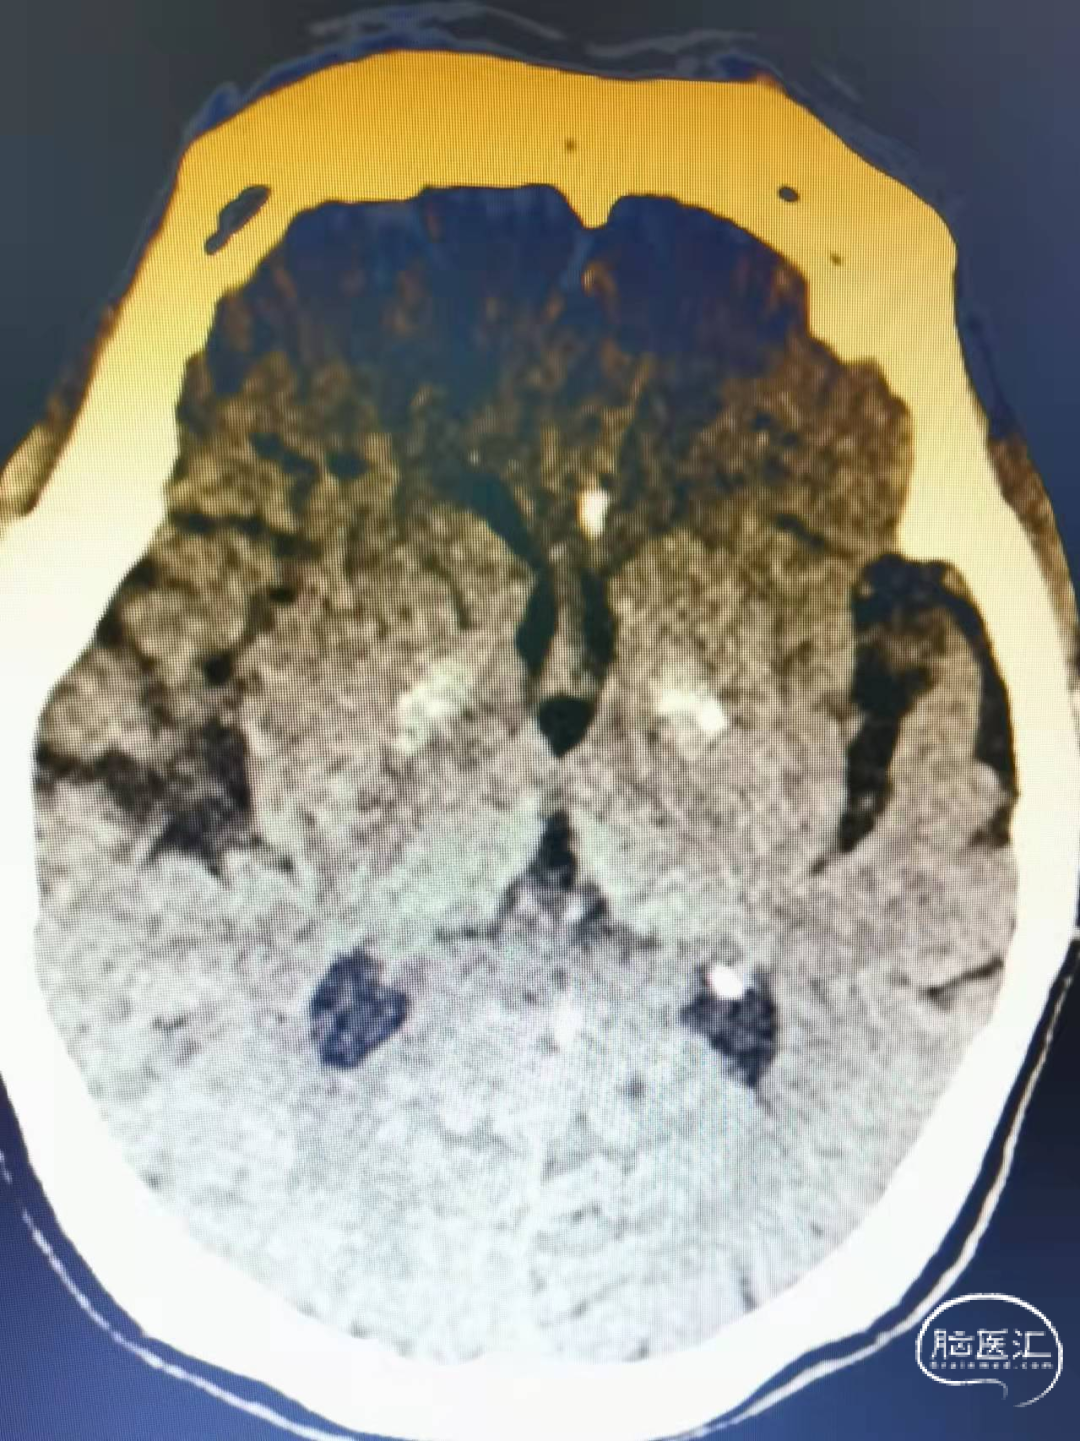

术前影像

头颅CT:左侧内囊后肢腔隙性脑梗死。

头颅MRI:双侧脑室旁异常信号。

头颅MRA:右侧大脑中动脉分叉部结节状突起。

DSA:右侧大脑中动脉分叉部动脉瘤,约3*5mm,颈宽约5mm,伴上下干起始部扩张。

大脑中动脉近端M1直径2.82mm,远端1.83mm,上干1.85mm,下干1.7mm。